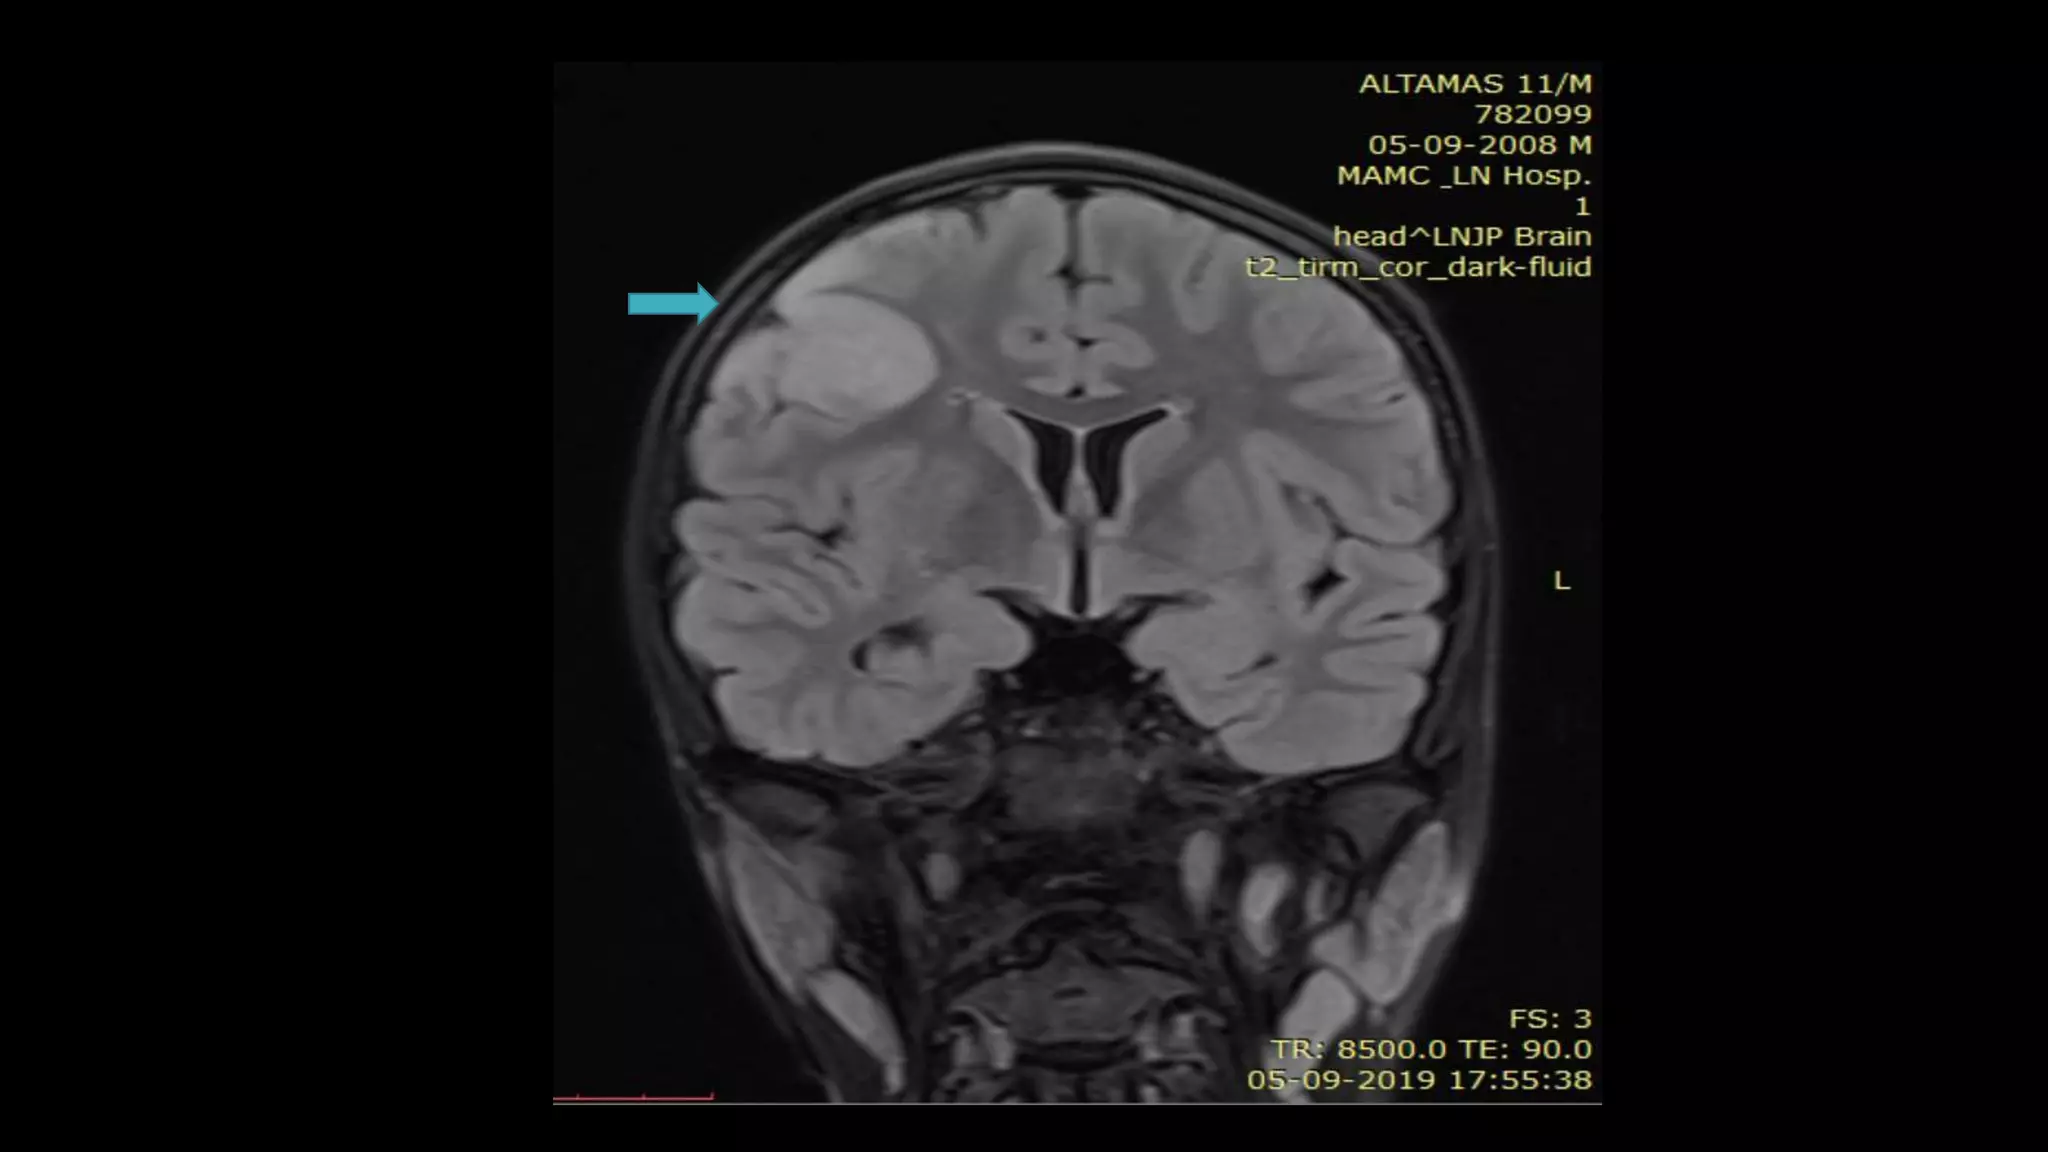

Head of right

caudate

nucleus and

lentiform

nucleus show

diffusion

restriction

• #46 Here is the example of the same patient shown before. DWI shows hyperintensity in the right frontoparietal region with hypointensity on corresponding ADC map s/o diffusion restriction